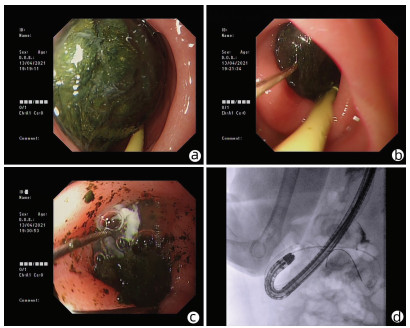

Successful treatment of Bouveret ' s syndrome due to giant duodenal gallbladder stones through the anterior wall of the stomach: A case report

Xu CHEN, Lunxu LI, Bing QI, Qingkai ZHANG, Guixin ZHANG, Shuang LI, Dong SHANG

2022, 38(3): 636-638. DOI: 10.3969/j.issn.1001-5256.2022.03.028

Abstract(896) HTML (227) PDF (2628KB)(43)

Abstract: